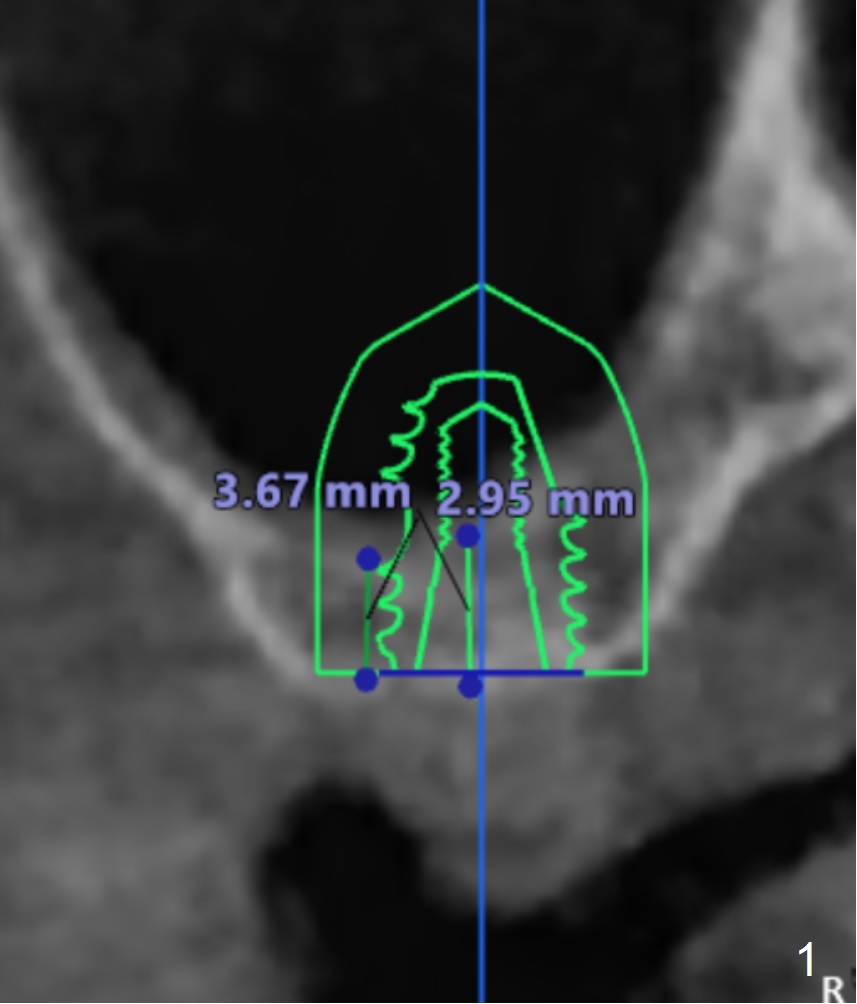

The implant size I tried was 5.0 X 7.3mm and it seems like bone density is quite low.

Undersized drilling suggested (at least 2 size smaller to get more fixation). And on the facial view there's 4mm of remaining bone but on the buccolingual view, there's less than 3mm. It would be much better if you could plan to do a lateral sinus elevation in this case.  Jennifer